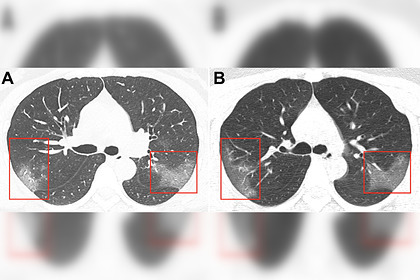

أحداث اليوم - عرض الأطباء الصينيون، صورا لرئتين مصابتين بفيروس كورونا 2019-nCoV.

وتم نشر نتائج التصوير الطبقي المحوري لمريضة تبلغ من العمر 33 عاما في مجلة Radiology وأشارت المجلة، إلى أن المرأة كانت تعمل في مدينة ووهان، حيث تم تسجيل انتشار الفيروس المميت لأول مرة.

وعلى أساس الخصائص الوبائية، والأعراض السريرية ونتائج التصوير الطبقي المحوري، تم تشخيص إصابتها بالالتهاب الرئوي 2019-nCoV.

وبعد ثلاثة أيام من العلاج، زادت المنطقة المصابة من الرئتين (الصورة ب) - في الصور تبدو معتمة.